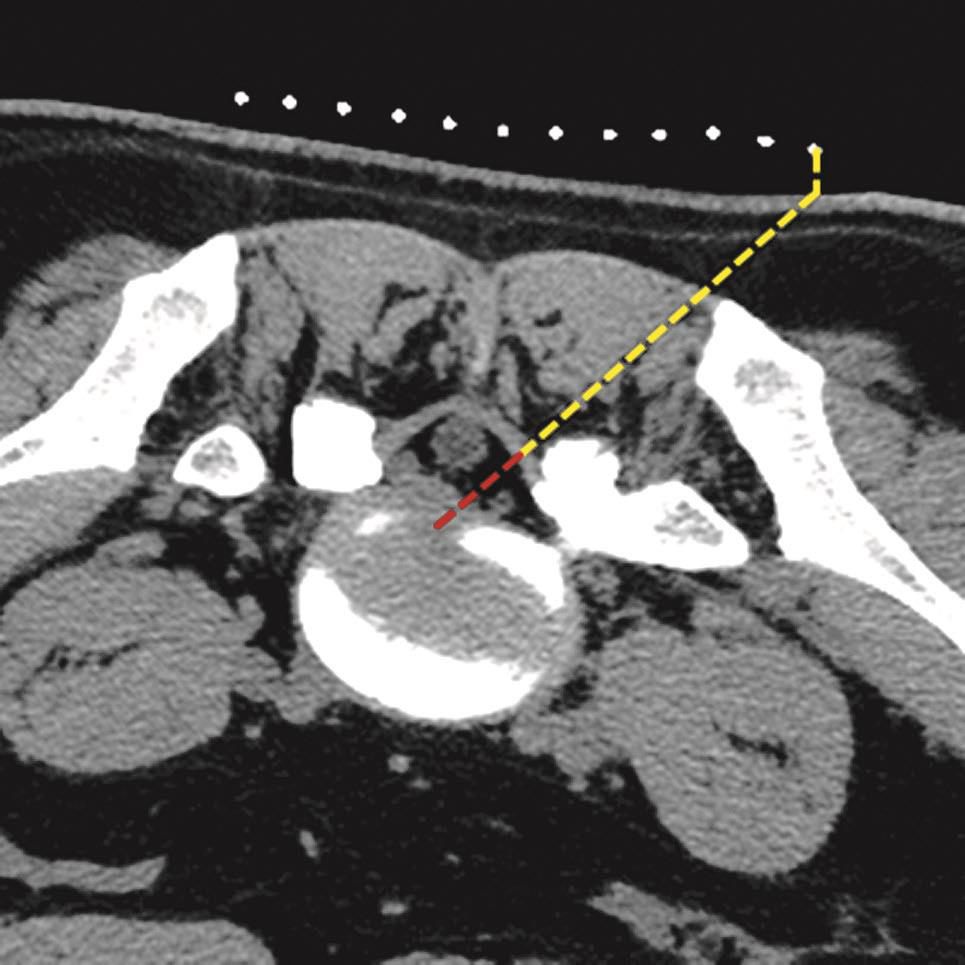

一般的CT机架可以调整角度(图3-3-8),调整机架角度进行扫描是寻找操作平面的关键举措,不同的穿刺途径和手术目的要求机架调整的角度也不同,如L 4/5 经椎间隙侧方入路时,如果手术平面无髂骨阻挡,则采用零度扫描(见图3-3-6A、图3-3-8B),否则为了避开髂骨阻挡,机架应向头侧倾斜(图3-3-6B、图3-3-8C);用于射频靶点消融或内镜髓核摘除的椎板间入路,如果扫描角度与椎间隙平行,将多有椎板阻挡(图3-3-9),其要点在于穿刺靶点为直接突出的椎间盘,而穿刺途径又必须避开椎板经过椎板间隙才能成功,因此要求调整到既能显示靶点又经过椎板间隙的角度,一般向足侧倾斜(图3-3-8A、图3-3-10);椎弓根入路则沿椎弓根轴线扫描(图3-3-11)。

在扫描产生的多层横断面中选择出最符合穿刺要求的一层,作为设计入路和引导穿刺定位的操作平面,我们将该层称为“靶点操作平面”。根据不同的手术目的选择该平面的要求也不同:避骨入路类手术如经椎板间入路椎间盘靶点定位类,应选择具有最大程度避开神经、血管、脏器、骨质而到达靶点的平面,如图3-3-12中显而易见图B是最合适的平面;经椎间隙侧方入路时的扫描图像中(图3-3-13),图B最合适;而经骨入路类手术如经皮椎体骨折复位外固定、椎体成形术等,应选择椎弓根宽大处的平面,如图3-3-14中图B作为操作平面最合适。CT机架角度扫描的横断位平面自然也是倾斜的,而穿刺定位入路是在该平面内的,因此存在如下关系:CT机架扫描角度=靶点操作平面角度=定位针穿刺时的头足倾斜角度(图3-3-15)。

图3-3-11 枢椎骨折沿椎弓根轴线扫描

图3-3-14 沿椎弓根轴线扫描的不同层

A.椎弓根偏头侧平面;B.椎弓根中间平面;C.椎弓根偏足侧平面